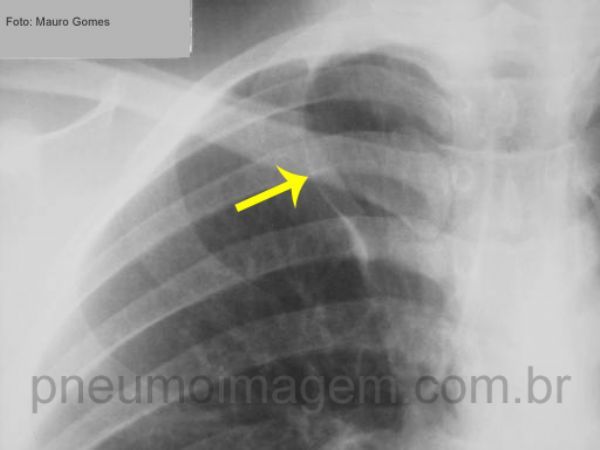

Lobo ázigos é uma variação anatômica presente em até 10% das pessoas

e sem relevância clínica. Forma-se a partir de um desenvolvimento anômalo do trajeto da veia ázigos, que desloca a pleura visceral em grau variável na região medial superior do lobo superior direito, originando um lobo acessório delimitado pela fissura ázigos (seta amarela).

Chaves: lobo acessório ázigos, cissura ázigos.

Azygos lobe is an anatomic variation present in up to 10 of people with no clinical relevance. It is formed from an anomalous development of the vena azygos, which displaces the visceral pleura in varying degrees in the upper medial right upper lobe.

Keys: accessory azygos lobe; azygos fissure (yellow arrow).